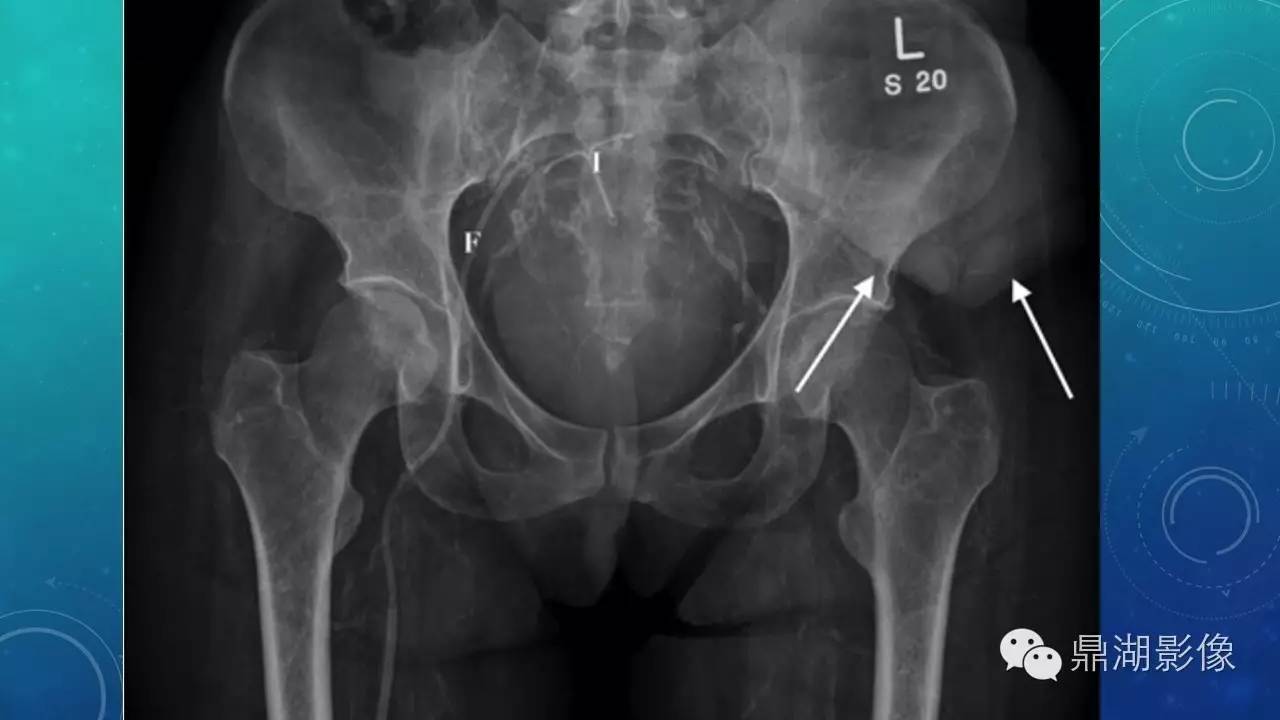

软组织钙化(的鉴别)